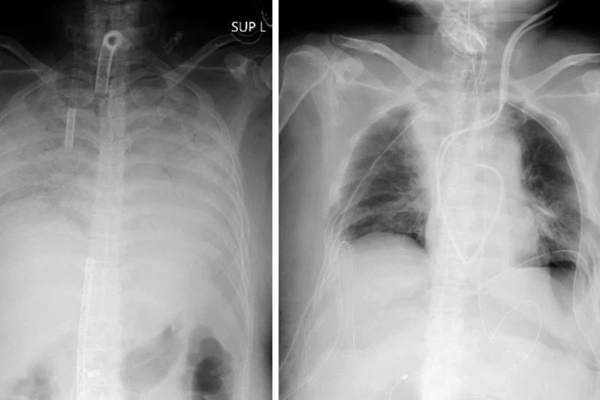

Ảnh chụp X-quang cho thấy phổi của một bệnh nhân COVID-19 trước và sau khi phẫu thuật cấy ghép. Ảnh: Bệnh viện Đại học Kyoto

Người phụ nữ sống ở miền tây Nhật Bản không có bệnh nền nhưng chức năng hô hấp của bà đã suy giảm nhanh chóng sau khi mắc COVID-19 vào cuối năm ngoái. Căn bệnh đã khiến cả hai phổi của bà co cứng lại và hầu hết các chức năng đều bị phá hủy. Khi các bác sĩ cho biết bà cần ghép phổi để sống sót, con trai và chồng bà đã quyết định hiến một phần phổi của họ. Họ đã được cảnh báo về những nguy cơ sức khỏe do giảm dung tích phổi.

Người phụ nữ nhập viện hôm 5/4 và được kết nối với một thiết bị tim phổi nhân tạo, được gọi là trao đổi oxy qua màng ngoài cơ thể (ECMO). Bà đã được ghép một phần phổi trái của chồng và một phần phổi phải của con trai hai ngày sau đó.

Toàn bộ quá trình cấy ghép phổi diễn ra khoảng 11 giờ đồng hồ tại Bệnh viện Đại học Kyoto. Các bác sĩ cho biết cả người hiến tặng và bệnh nhân đều trong tình trạng sức khỏe ổn định.